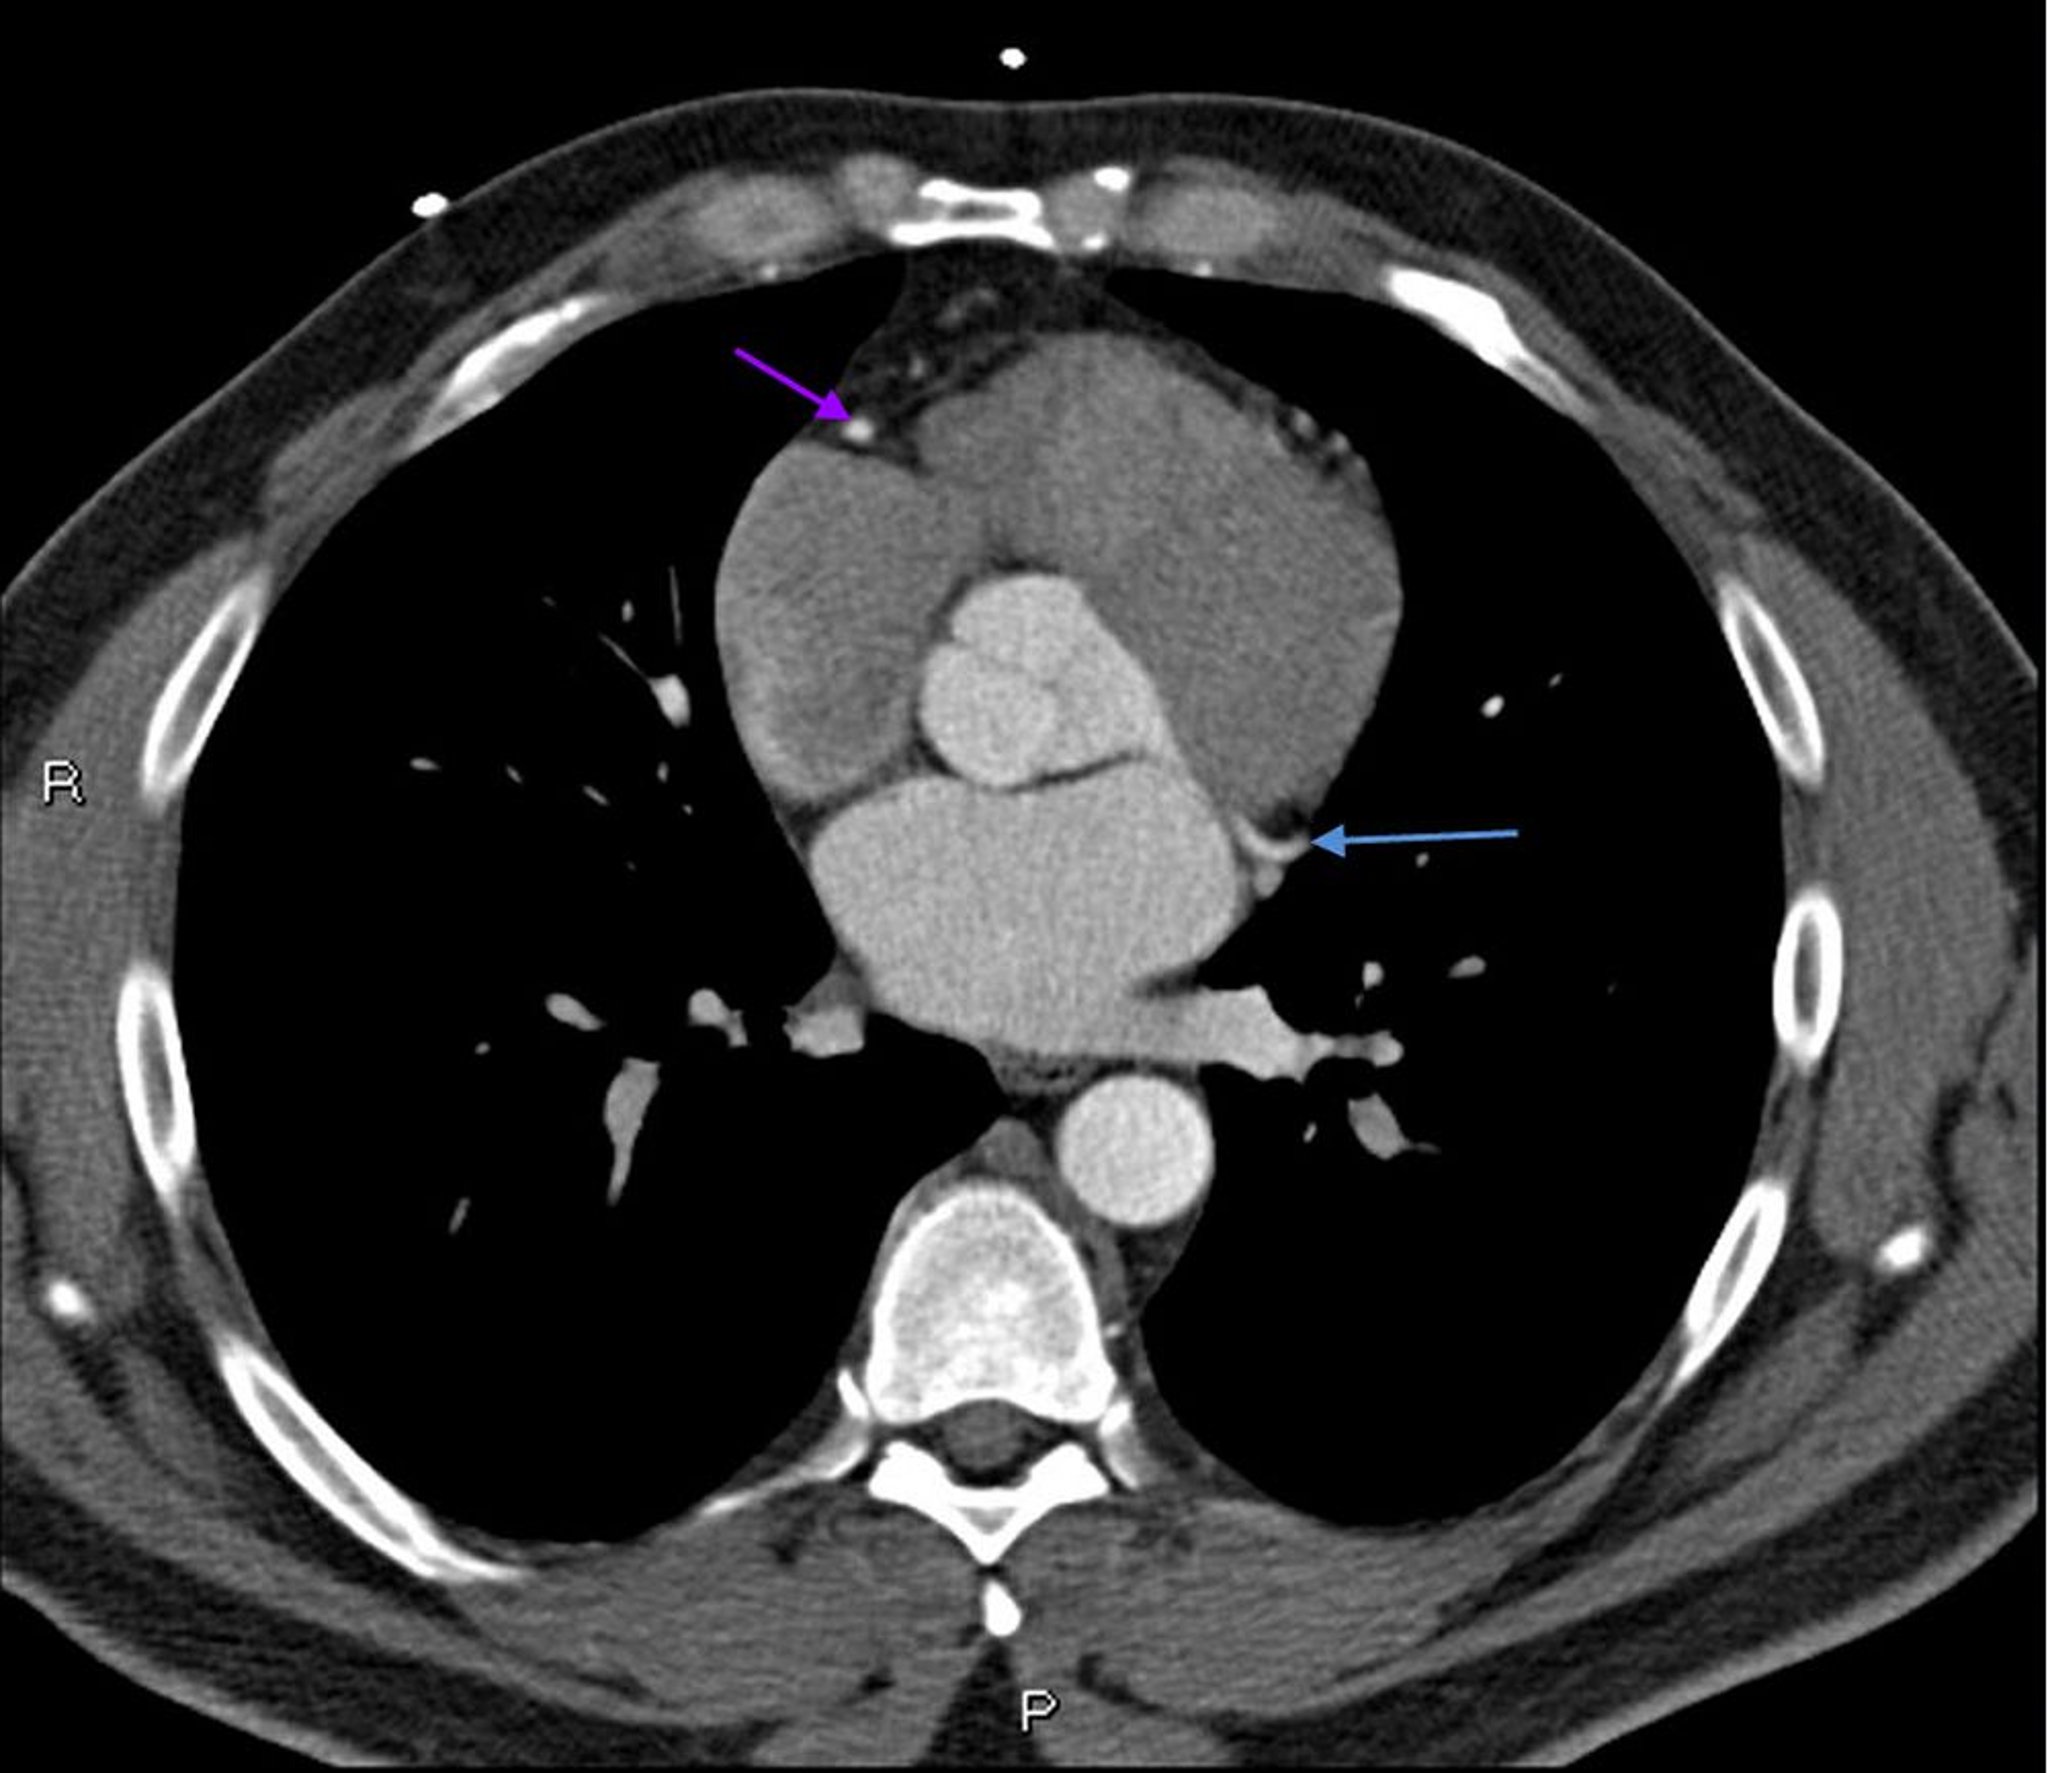

TDM avec contraste montrant des artères coronaires normales – Coupe 6

Cette TDM avec contraste montre des artères coronaires normales. Le tronc commun coronaire gauche est indiqué par la flèche rouge. Les artères interventriculaire antérieure gauche et circonflexe gauche sont indiquées par les flèches verte et bleue respectivement et l'artère coronaire droite est indiquée par la flèche violette.